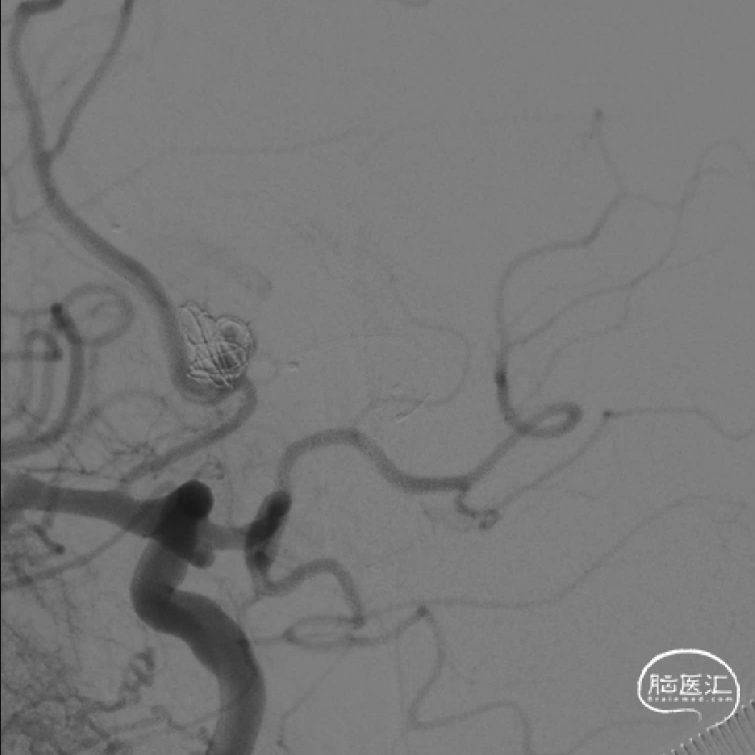

术后影像

释放支架后继续填塞至动脉瘤不显影。双侧A1-A2显影良好。患者术后神经体检正常。